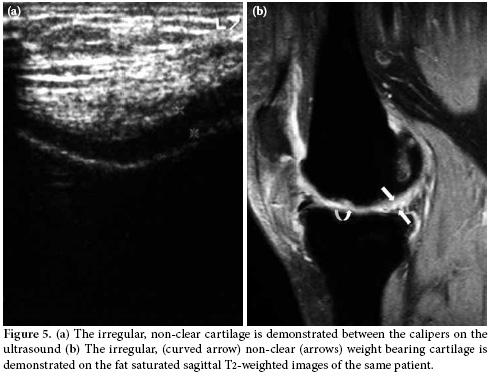

In the second position, the weight bearing medial and lateral femoral condylar cartilage thickness and clarity were evaluated with the knee in maximum flexion. The femoral condylar cartilage was measured on the weight-bearing area approximately 1.5 cm away from the intercondylar notch (Figure 3). The cartilage morphology was assessed using a scale: 1 for regular-clear (Figure 4a, b) and 0 for irregular, non-clear (Figure 5a, b). Finally, all the patients were evaluated for popliteal cysts with the knee extended in a prone position, and any presence of popliteal cysts was recorded.

It is known that a normal femoral condylar cartilage has a clear, smooth and homogeneous hypoechoic appearance parallel to that of the cortical bone on US. Ultrasound has great potential to identify the normal cartilage and allows for differentiation of the abnormal morphology such as loss of clarity, irregularity, and defects on the surface.[7,19] We believe that in the present study, the high concordance rates with MRI have confirmed the accuracy of US in the assessment of cartilage morphology contrary to cartilage measurements.